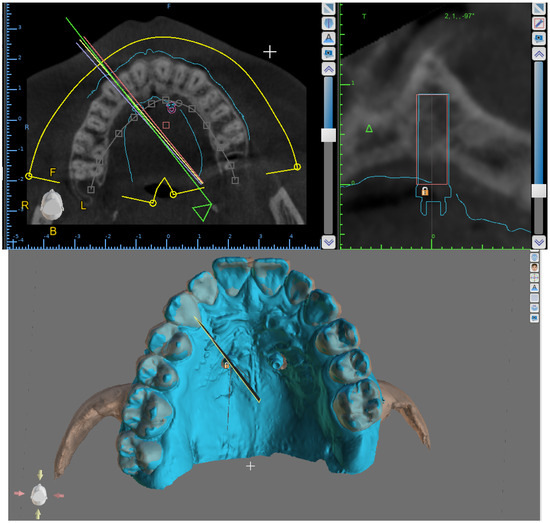

2. Materials and Methods